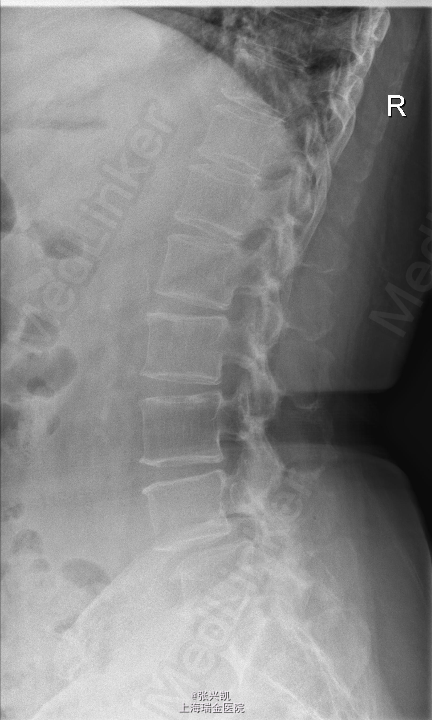

主诉:腰痛伴下肢疼痛3年余,近期双下肢疼痛加重 现病史:患者10年前出现腰痛,症状可自行缓解,未予重视,3年前出现腰痛伴双下肢疼痛,右侧为重,3个月来无明显诱因,症状加重,患者因腿痛无法正常行走,需借助一定器械、外物,弯腰前倾行走。

查体:脊柱无侧弯畸形,无叩痛压痛,上肢感觉肌力正常,双下肢疼痛,右侧较重,小腿前外侧感觉异常,下肢肌力4-5级,跟膝腱反射(+),巴氏征(-) 辅助检查:X线动力位示:L4椎体滑脱,腰椎退行性改变 MR:L4椎体向前I°滑脱,L3-5椎间盘突出,椎管狭窄

诊断:腰椎椎管狭窄L4-5 L4椎体滑脱 处理:腰椎后路减压复位融合内定术